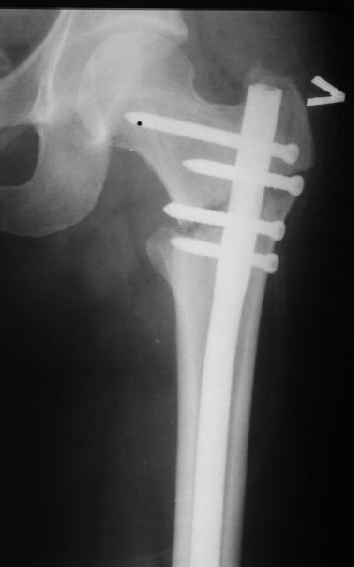

Конечно, мы не синтезируем остеопорозые вертельные переломы согласно прилагаемому примеру, винты 6 мм вырежутся. Но у более молодых при хорошем качестве кости такие или подобные гвозди с поперечным расположением винтов вполне применимы для меж- и подвертельных переломов.

Это было года 2,5 назад, мы тогда еще уточняли возможности шинирования с угловой стабильностью гвоздем с поперечным расположением винтов при переломах проксимального отдела бедра. Пациенту не пришлось приобретать намного более дорогой рекон или проксимальный гвоздь. В приложении еще несколько примеров применения того гвоздя при высоких переломах бедра, в том числе с более латеральной точкой входа. Гвоздь изгибаем для этого.